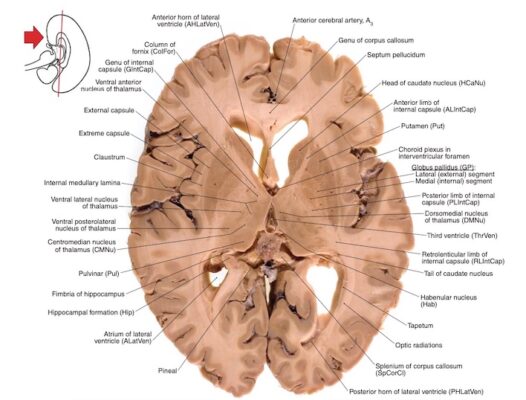

Bao trong nằm ở phần trong dưới của mỗi bán cầu. Trên thiết đồ cắt ngang não, bao trong có hình chữ V với đỉnh hướng vào trong.

Bao trong chứa các sợi phóng chiếu (chất trắng) quan trọng đi đến và đi từ vỏ não. Bao trong có thể được chia thành ba vùng khác nhau.

- Chi trước (anterior limb) nối vỏ não thuỳ trán với đồi thị và cầu não và các sợi đồi thị đến thuỳ trán.

- Gối/góc của bao trong (genu) chứa các sợi vận động vỏ não đi đến các nhân vận động ở thân não (corticobulbar fibers).

- Chi sau (posterior limb) chứa các sợi vận động từ thuỳ trán tạo thành bó vỏ gai (corticospinal tract) và các sợi cảm giác chiếu từ đồi thị đến thuỳ đỉnh của vỏ não. Chi sau cũng chứa các sợi thị giác và thính giác chiếu từ đồi thị đến thùy chẩm và thùy thái dương tương ứng.

CÁC HẠCH NỀN (BASAL GANGLIA)

Là các khối chất xám nằm trong chất trắng dưới các não thất bên. Do vị trí nằm ở đáy não (base) nên được gọi là hạch nền. Danh xưng hạch nền đôi lúc gây nhầm lẫn, tên đúng ra phải là các nhân nền (hạch là nhóm tế bào thần kinh ngoại biên, nhân là nhóm các tế bào thần kinh trung ương).

Các cấu trúc của hạch nền bao gồm nhân đuôi (caudate nucleus), bèo sẫm (putamen), cầu nhạt (globus pallidus), chất đen (substantia nigra, nằm ở não giữa), và nhân dưới đồi (subthalamic nuclei). Cầu nhạt và bèo sẫm tạo thành nhân bèo (lentiform nucleus), còn nhân đuôi và bèo sẫm được gọi là thể vân (striatum).

Nhân đuôi và bèo sẫm là các nhân nhận tín hiệu đầu vào chính của hạch nền, từ các vùng rộng của vỏ não mới, bao gồm cảm giác, vận động và các vùng liên hệ.

Cầu nhạt nằm ngay phía trong bèo sẫm và gồm hai phần (ngoài và trong). Chất đen (ở não giữa) và phần trong của cầu nhạt là các vùng đầu ra chính của hạch nền. Đầu ra tận cùng ở các vùng vỏ não trước trán, vùng vận động bổ sung và vùng tiền vận động qua trung gian đồi thị, để điều chỉnh tư thế và trương lực cơ, cũng như các vận động theo ý muốn và tự động.